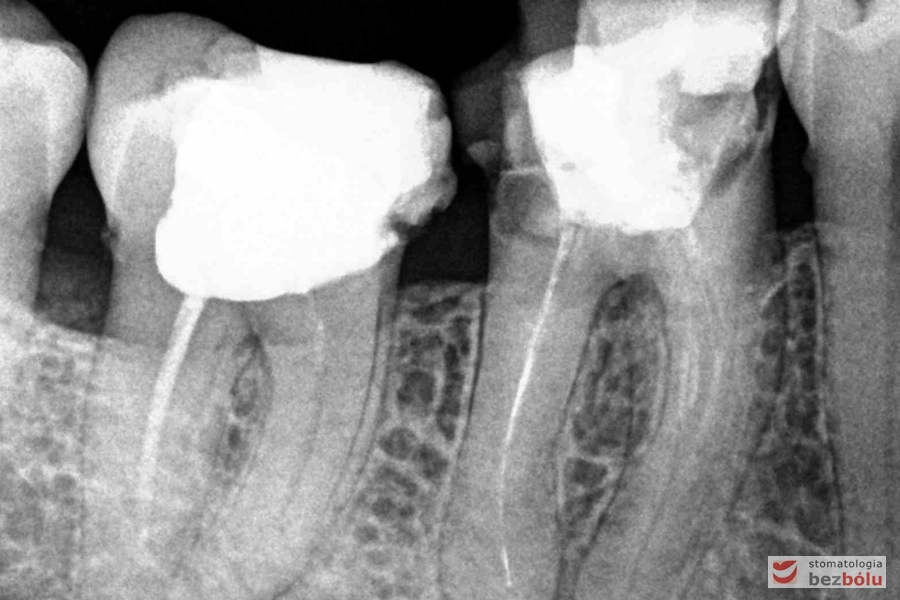

Radiowizjografia - szóstka, piątka, czwórka prawa w szczęce, wszystkie kanały niedopełnione

Radiowizjografia – szóstka, piątka, czwórka prawa w szczęce, wszystkie kanały niedopełnione